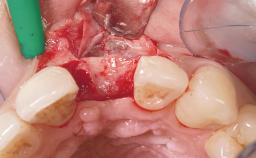

Late Flapless Placement of an Implant in a Maxillary Left Central Incisor Site

A 39-year-old male patient presented with a chief complaint of discomfort and gingival discoloration around his maxillary left central incisor. He was in good general health and was a non-smoker. His past dental history was significant because of the traumatic fracture of tooth 21 in a sporting accident at age 13. Initial dental treatment included endodontic therapy and a full-coverage restoration. The patient became symptomatic 5 years later, when structural failure of the tooth resulted in the dislodgment of the crown. Endodontic retreatment, apical surgery, and post-and-core restoration were performed.

| Bone Augmentation | Horizontal|Staged |

| Augmentation Materials | Xenogenous|Membrane |

| Soft Tissue Grafting | Simultaneous |